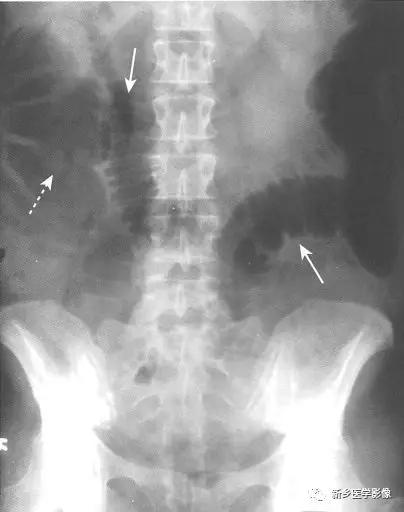

梗阻近端结肠扩张。

由于大肠肠襻数目有限,且不互相重叠(如小肠肠襻),所以有时可以通过观察最后含气的结肠肠段来确定梗阻部位。

不论肠梗阻部位在何处,盲肠往往是结肠的扩张最严重的肠段,当盲肠直径达到15cm以上时,须警惕盲肠破裂的风险。

小肠不扩张(除非回盲瓣功能不全)。

因为直肠常常位于梗阻部位以远,所以直肠内包含很少气体或没有气体。

由于大肠具有重新吸收水的功能,大肠内通常没有或很少气-液平面。